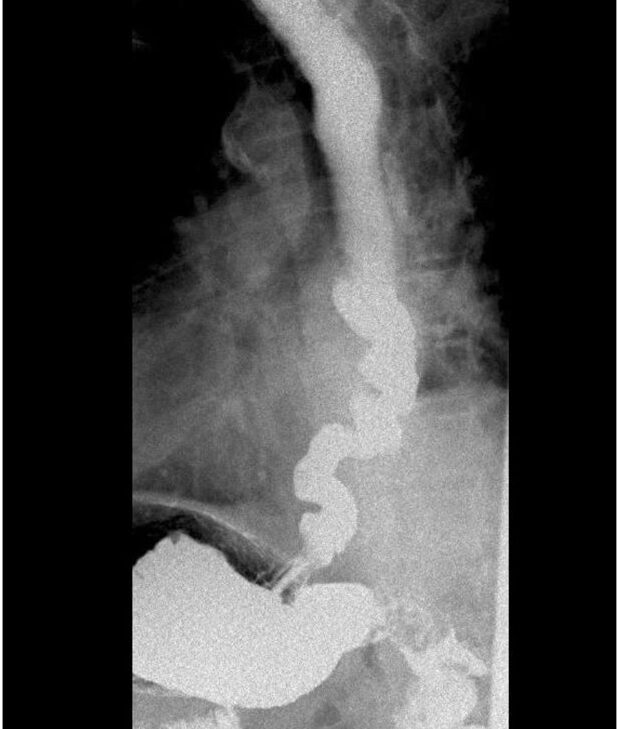

Varón de 84 años, con antecedentes de hipertensión arterial, dislipemia, cardiopatía isquémica crónica, carcinoma de próstata tratado con radioterapia, en remisión desde 2013, y síndrome de aceite tóxico por intoxicación con aceite de colza en 1981. Es derivado a nuestras consultas por disfagia para sólidos y líquidos de unos 30 años de evolución, que ha empeorado en los últimos 5 años, con episodios de impactaciones que se resuelven con la ingesta de agua. Asocia regurgitaciones líquidas y, de forma puntual, dolor torácico. El paciente relaciona el inicio de los síntomas con la intoxicación por aceite de colza. En la endoscopia digestiva alta se visualiza un esófago con mucosa de aspecto normal con morfología de sacacorchos (figura 1), con ondas terciarias no propulsivas y con cierta resistencia al paso del endoscopio a través de la unión esofagogástrica (UEG). Se toman biopsias esofágicas que no presentan alteraciones. [caption id="attachment_6748" align="alignnone" width="1044"]

Figura 1. Endoscopia digestiva alta. Esófago con morfología en sacacorchos

Por el contrario, en nuestro paciente la gastroscopia y el esofagograma realizados mostraron características típicas del espasmo esofágico distal y la manometría esofágica una presurización panesofágica similar a la observada en la acalasia tipo II.